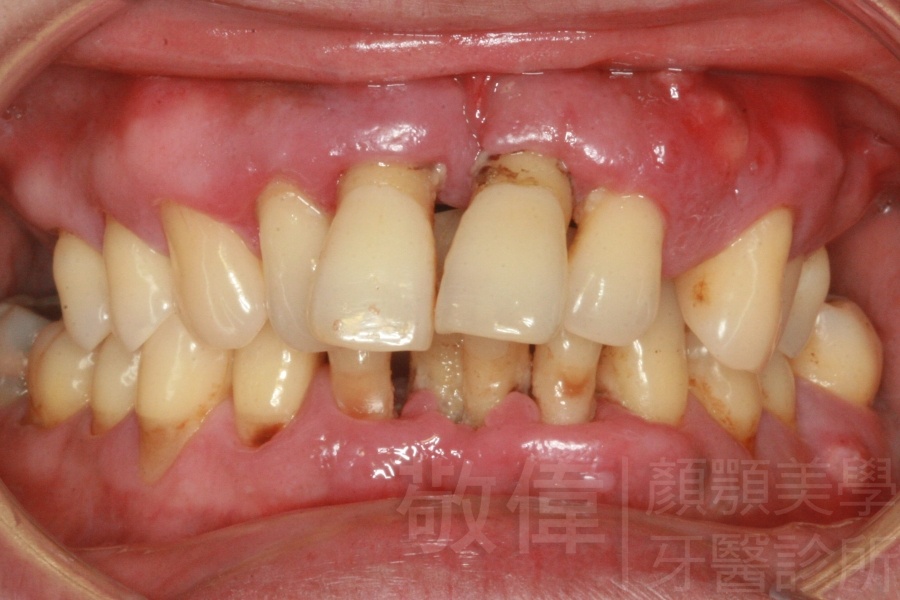

人工植牙/因嚴重牙周病而缺牙的植牙重建

嚴重牙周病   拔除牙周病牙齒